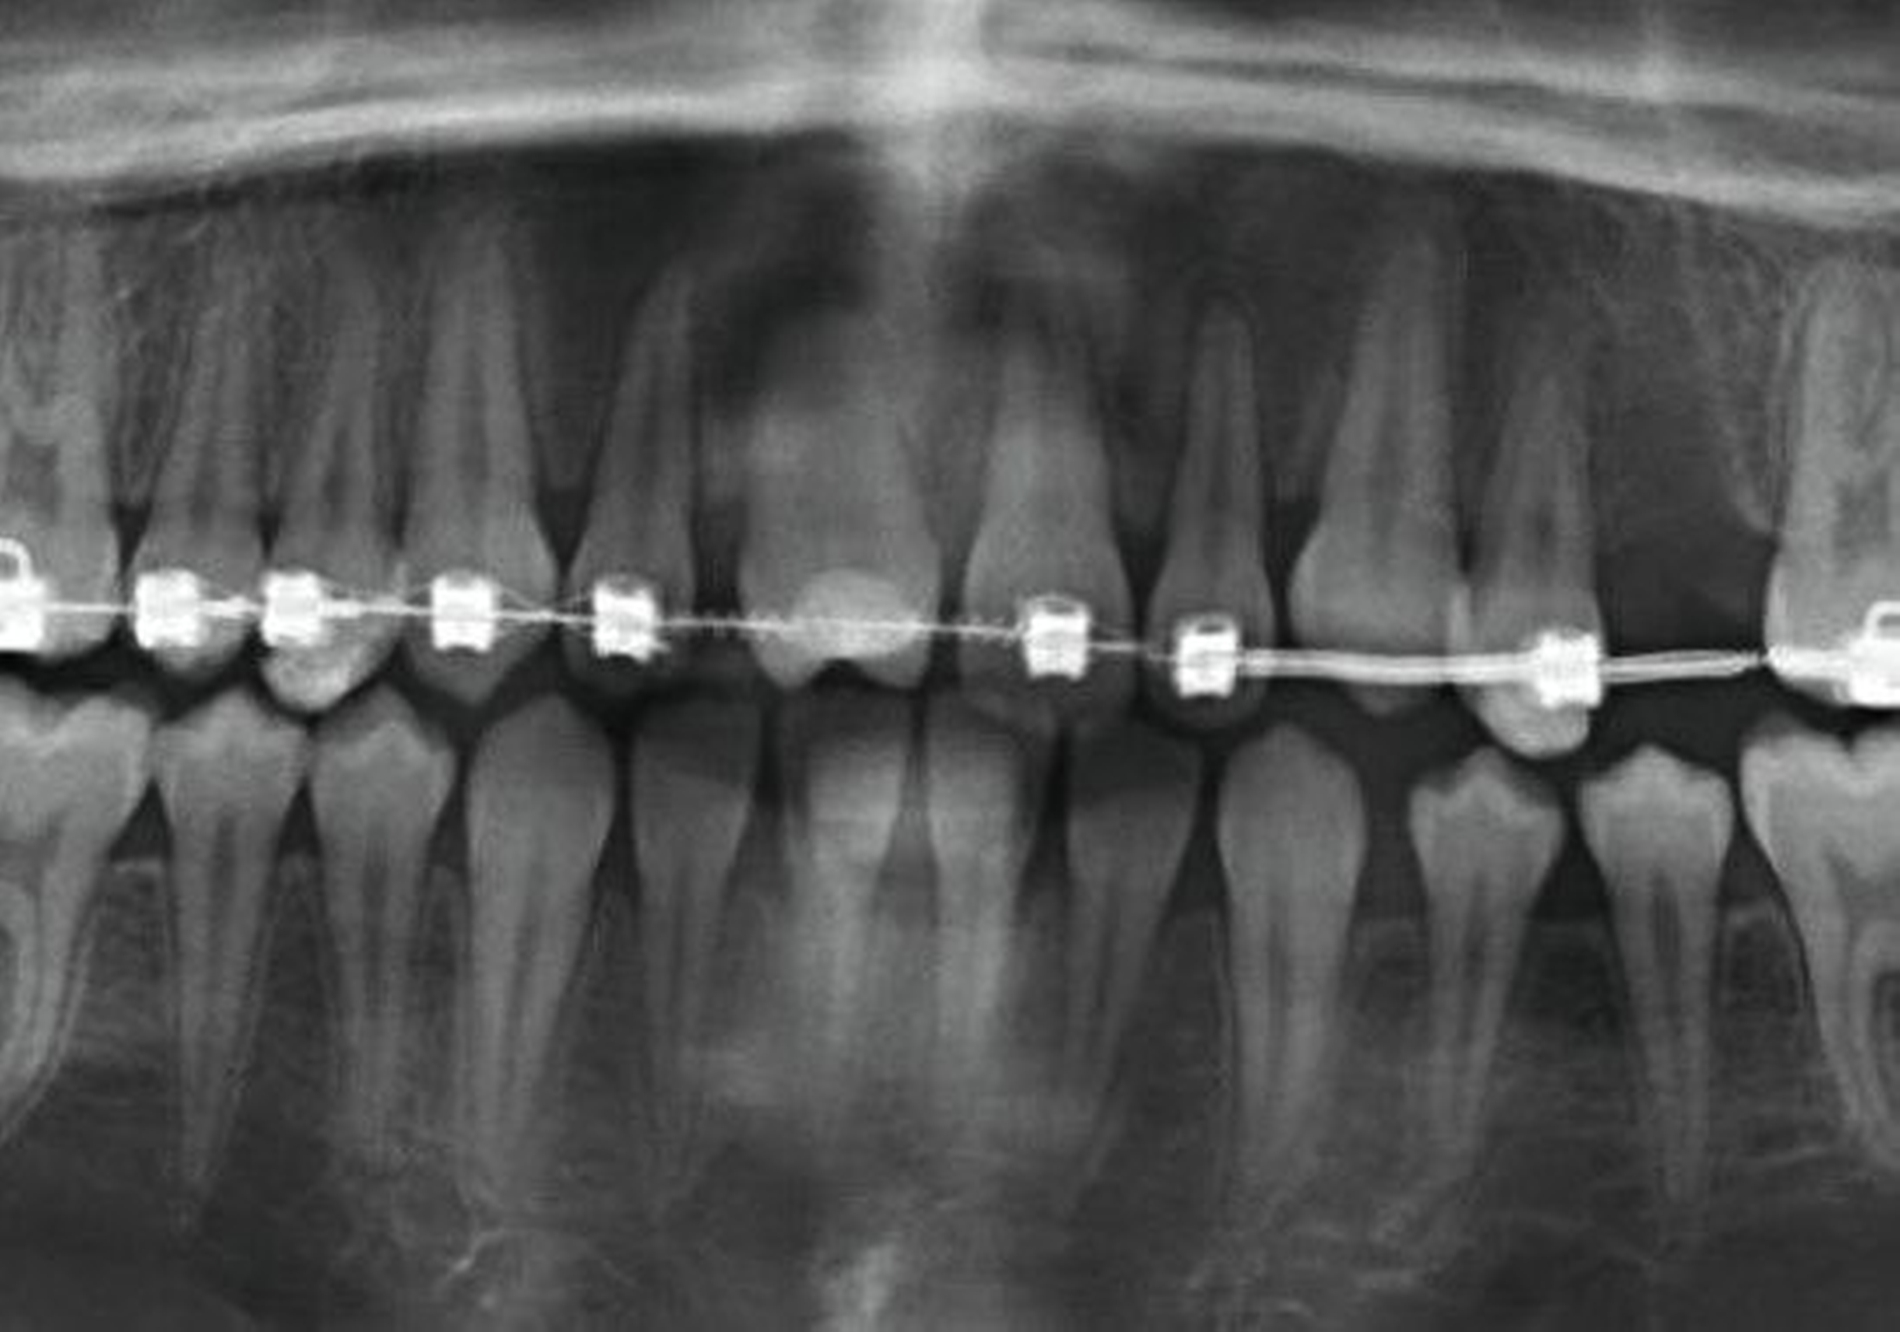

Eine Dekoronation ist eine chirurgische Intervention, die durchgeführt werden kann, wenn aufgrund ausgeprägter Schädigungen der desmodontalen Zellen und der Wurzeloberfläche eine Resorption auftritt. Im Rahmen der klinischen Untersuchung imponiert der betroffene Zahn aufgrund der Ankylose mit einem metallischen (hellen) Klopfschall. Röntgenologisch lassen sich Resorptionslakunen an der Wurzeloberfläche erkennen. Bei progressiver Resorption und Infraposition des betroffenen Zahnes in Relation zur Restdentition kann eine Dekoronation indiziert sein [Malmgren et al., 2015] (Abbildung 2).

Das Ziel der Dekoronation ist es, die klinische Krone unter Belassung der resorbierenden Wurzel zu entfernen, damit der Alveolarknochen aufgrund der Knochenneubildung bei Ersatzresorption erhalten und eine optimale Voraussetzung für spätere Interventionen gegeben werden kann [Malmgren et al., 2006]. Bei Patienten im Wachstum kann die Dekoronation eine sinnvolle Therapieoption darstellen, um den teils erheblichen Knochenverlust in Verbindung mit der chirurgischen Entfernung der ankylosierten Zahnwurzel zu vermeiden (Empfehlung 60).